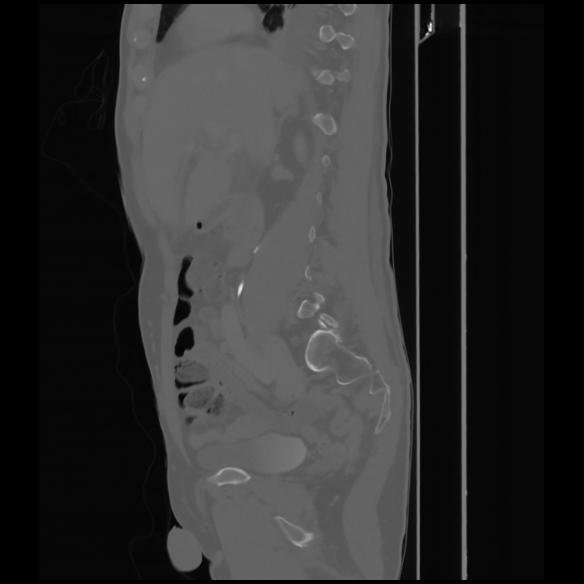

7 CUERPO,CE,Sagittal,3.000,CUERPO,Sagittal,